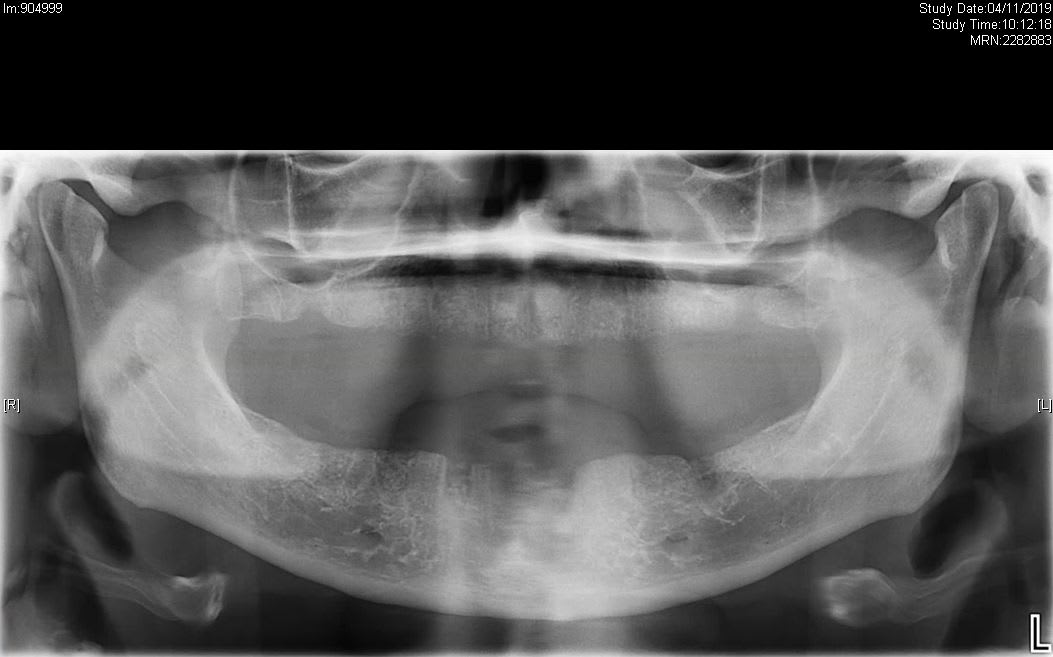

Les autres ont déjà bien identifié le surtraitement qui explique les pano 1 et 2, mais il leur manque un élément qui explique le passage à la 3 et la consult en urgence.

3ème RDV ce jour. La patiente a quand même fait enlever les implants en Turquie de nouveau; évidemment les douleurs persistent. Évidemment ce jour rien à signaler, muqueuses parfaitement saine, aucun signe infectieux ou inflammatoire en bouche ou autour. Adressée vers le centre de gestion de la douleur locale avec soupçon de névralgie, possible lésion liée à la chirurgie.

Bref, une jolie combinaison de surtraitement, tourisme dentaire, et douleur d'origine inconnue comme on les aime.